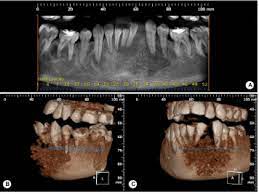

Jaw cancer results in pain in the area with difficulty in opening the mouth. As you review these images and their descriptions, you. Usually it's spotted first by your dentist, so keeping regular dental exams can help with early detection. What bone metastasis looks like. It will show the normal anatomy of the bone and the additional growth arising from the bone and we can see the exact dimensions of the cancer and its local extent of spread and invasion into the surrounding tissues. With time they may spread inside the mouth and on to other areas of the head and neck or other parts of the body. Early on, the pain may only occur at night, or when you are active. Each tumor looks like it's the original site of disease on the scans, suggesting that the bone tumors developed independently, at the same time, at multiple sites. This can lead to insomnia, loss of appetite, and inability to carry out normal daily activities. At first the ulcer is painless, but it later becomes painful. People with a fracture next to or through a bone tumor usually describe sudden severe pain in a bone that had been sore for a few months. Tongue cancer is a type of cancer that starts in the cells of the tongue, and can cause lesions or tumors on your tongue. Cancer in the bones of the spine can press on nerves, causing numbness and tingling or even.

Each tumor looks like it's the original site of disease on the scans, suggesting that the bone tumors developed independently, at the same time, at multiple sites. It is a good imaging: At first the ulcer is painless, but it later becomes painful. Buccal mucosa is another name for the inside lining of the cheeks. The appearance of feline oral cancer can vary significantly, depending on the type of cancer and how far advanced the cancer is.

Metastatic Tumors To The Jaws A Report Of Eight New Cases from scielo.isciii.es Some of the most common oral cancer symptoms and signs include: Chemotherapy, hormone therapy, and immunotherapy target the main cancer. Other conditions, like osteoporosis or arthritis, may also cause bone or joint pain. Malignant cells in the jaw tend to spread quickly to adjacent organs. The sore may be red or white and may look like a thickening of the gum. At first the ulcer is painless, but it later becomes painful. Soft palate cancer starts in the soft palate cells, which are on the upper portion of the back of your mouth, right behind your teeth. The ulcer may bleed as the cancer grows.

Unlike hard palate cancer, soft. Tongue cancer is a type of cancer that starts in the cells of the tongue, and can cause lesions or tumors on your tongue. Typically, a blood clot forms over your empty socket. People with a fracture next to or through a bone tumor usually describe sudden severe pain in a bone that had been sore for a few months. Treatment for bone cancer in dogs can vary depending on which bones are affected. Abnormal cell growth usually appears as flat patches. A large amount of bone and tissue surrounding the tumor may also have to be removed to eliminate the majority of cancerous cells at the site. Lumps on the roof of your mouth or along your gumline may be the only jaw cancer symptoms you experience. These cancers usually occur in the thin, flat cells called squamous cells that line the buccal mucosa and other parts of the mouth. Gum cancers may start out looking like a bump or a sore that does not heal. Bone cancer can weaken the bone it's in, but most of the time the bones do not fracture (break). It's a type of head and neck cancer. Cancer in the bones of the spine can press on nerves, causing numbness and tingling or even.